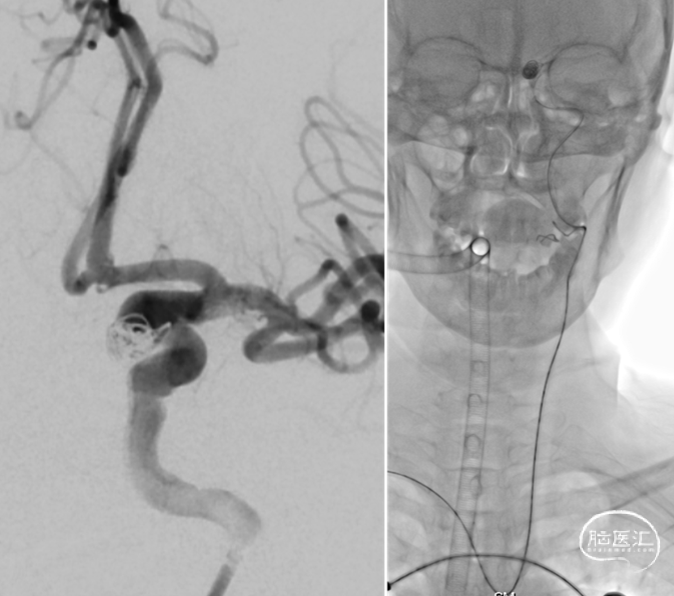

术前DSA:左侧颈内动脉床突旁动脉瘤,形态不规则,大小约5.7mm x 5.9mm。

右侧桡动脉穿刺,穿刺成功后置入6F薄壁动脉鞘,随后使用TRUST技术置入Tethys®中间导引导管(内衬5F Simmon导管)输送至锁骨下动脉,弓上勾选至左侧颈总动脉后,Tethys®中间导引导管顺滑输送至左侧颈内动脉成功建立治疗通路,为后续致密栓塞及释放支架提供重要支撑.

建立治疗通路后,在微导丝引导下分别将塑性好的弹簧圈微导管及支架微导管超选至左侧颈内动脉床突旁动脉瘤及左侧大脑中动脉远端;释放支架后,填入弹簧圈实现动脉瘤的致密填塞;在整个过程中Tethys®中间导引导管提供稳定支撑。

术后造影提示动脉瘤内弹簧圈致密填塞,动脉瘤不显影,瘤颈封堵可,左侧颈内动脉通畅。